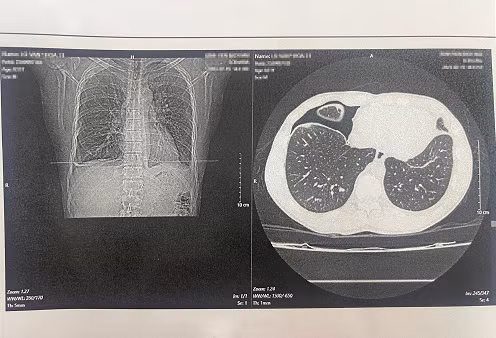

![]() |

| Hình ảnh phim chụp trên bệnh nhân nhiễm sán lá phổi. Ảnh: Bệnh viện cung cấp |